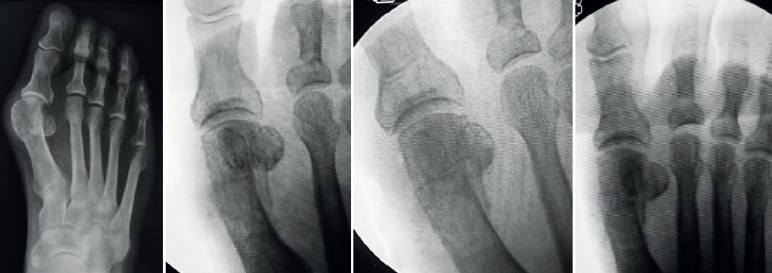

Como vemos, la sugerencia de algún tipo de estabilización debido al riesgo de desplazamiento de la cabeza metatarsiana, menor dolor y edema es una constante en las mencionadas publicaciones. Este concepto es discutible debido a que la osteotomía de tipo Chevron realizada con la rama plantar larga y paralela al piso es intrínsecamente estable y compatible con un postoperatorio de carga precoz (Figuras 4A, B y C) al igual que las osteotomías “con fijación”(17). Los problemas relacionados con el uso de osteosíntesis en las osteotomías metatarsianas ascienden al 10-15% en diferentes series(3,9,11).

Uno de los aspectos importantes en cuanto a la posición de la cabeza metatarsiana es el referente al plano sagital. Pocos trabajos de tratamiento de hallux valgus evalúan el ascenso de la cabeza. En este grupo de pacientes hemos observado que el ascenso de la cabeza es solo de 1,03 mm como promedio y no encontramos en la evolución alguna repercusión clínica asociada con dicho ascenso (Figura 5). Otro aspecto de la osteotomía en Chevron es que históricamente ha sido usada para la corrección de hallux valgus leves a moderados por su ubicación intraarticular, como es la forma clásica abierta o la moderna PeICO(11,12,13). Una de las modificaciones propuestas en este trabajo es hacer la osteotomía PECU a 7 o 10 mm proximal al centro geométrico de la cabeza (ubicación extraarticular), lo que nos permite un mayor desplazamiento y mejora el poder de corrección, asemejándose a una osteotomía diafisaria, como describen autores como Redfern, Vernois, Lee, Hernández, Bauer o Laffenétre en modelos de Chevron percutánea con fijación(3,4,5,9). En este trabajo fueron tratados hallux valgus graves (HV°> 40° e IM° > 16°) de forma satisfactoria.